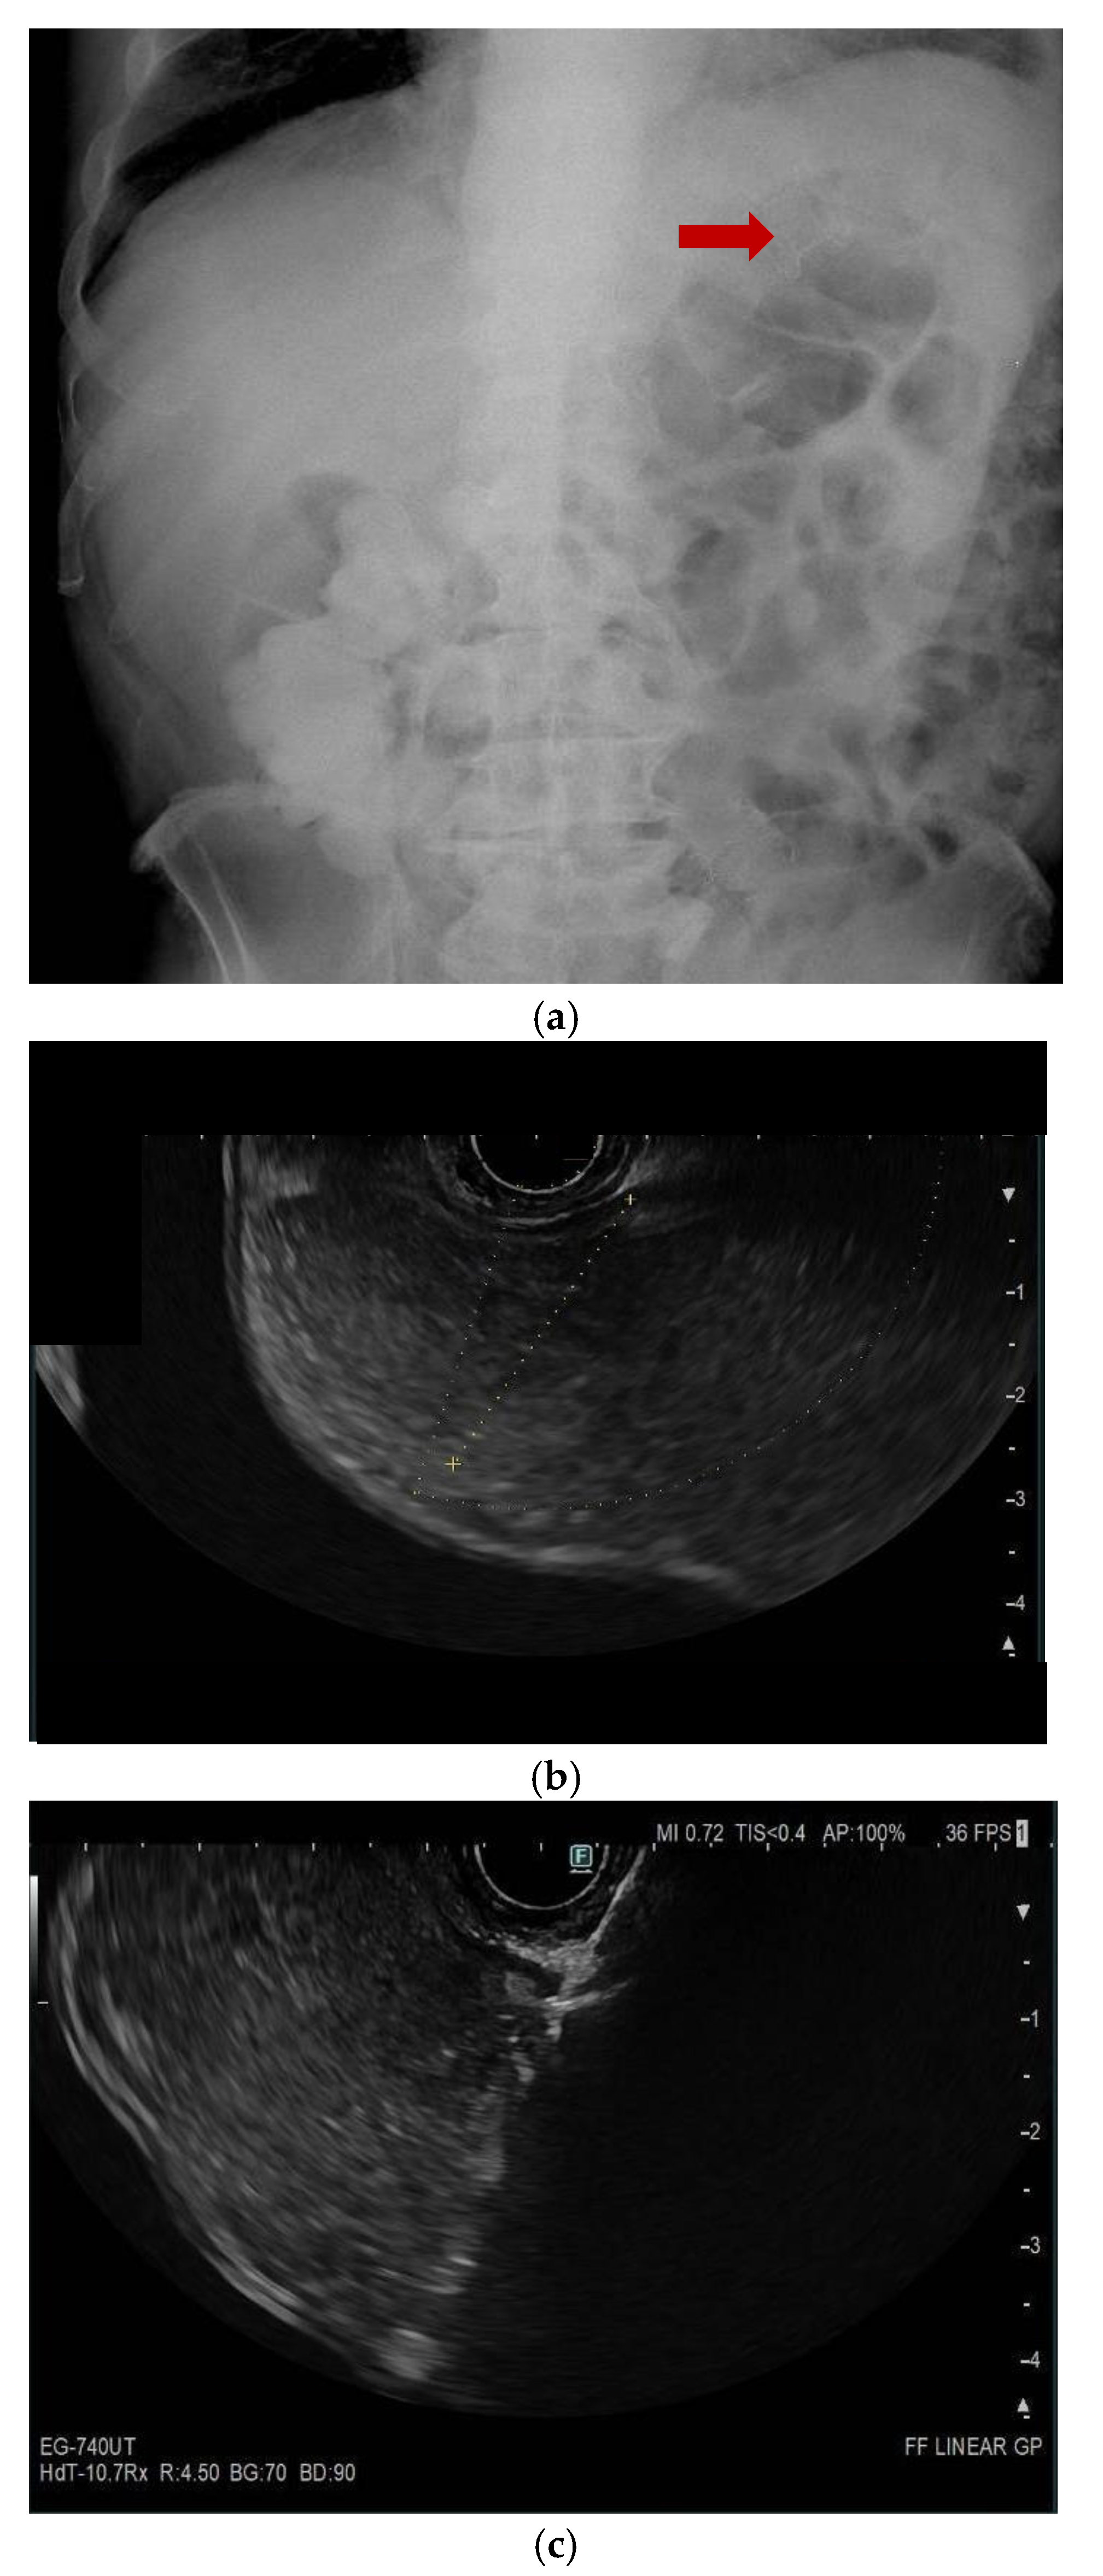

6. Percutaneous Techniques

10. Endoscopic Ultrasound-Guided Entero-Colostomy with LAMS